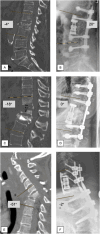

Methods: This retrospective single-center study examined 100 consecutive cases (2015-2022) that underwent VBR for spinal infection treatment. A comparison between Single-level-VBR and Multi-level-VBR was performed, evaluating patient profiles, revision rates, and outcomes.

Results: Among 360 cases treated for spinal infections, 100 underwent VBR, located in all spinal regions. Average clinical and radiologic follow-up spanned 1.5 years. Single-level-VBR was performed in 60 cases, Two-level-VBR in 37, Three-level-VBR in 2, and Four-level-VBR in one case.Mean overall sagittal correction reached 10° (range 0-54°), varying by region. Revision surgery was required in 31 cases. Aseptic mechanical complications (8% pedicle screw loosening, 3% cage subsidence, 6% aseptic adjacent disc disease) were prominent reasons for revision. Longer posterior constructs (>4 levels) had significantly higher revision rates (p < 0.01). General complications (wound healing, hematoma) followed, along with infection relapse and adjacent disc infection (9%) and neurologic impairment (1%).Multilevel-VBR (≥2 levels) displayed no elevated cage subsidence rate compared to Single-level-VBR. Three deaths occurred (43-86 days post-op), all in the Multi-level-VBR group.

Conclusion: This study, reporting the largest number of VBR cases for spinal infection treatment, affirmed VBR's effectiveness in sagittal imbalance correction. The overall survival was high, while reinfection rates matched other surgical studies. Anterior procedures have minimal implant related risks, but extended dorsal instrumentation elevates revision surgery likelihood.